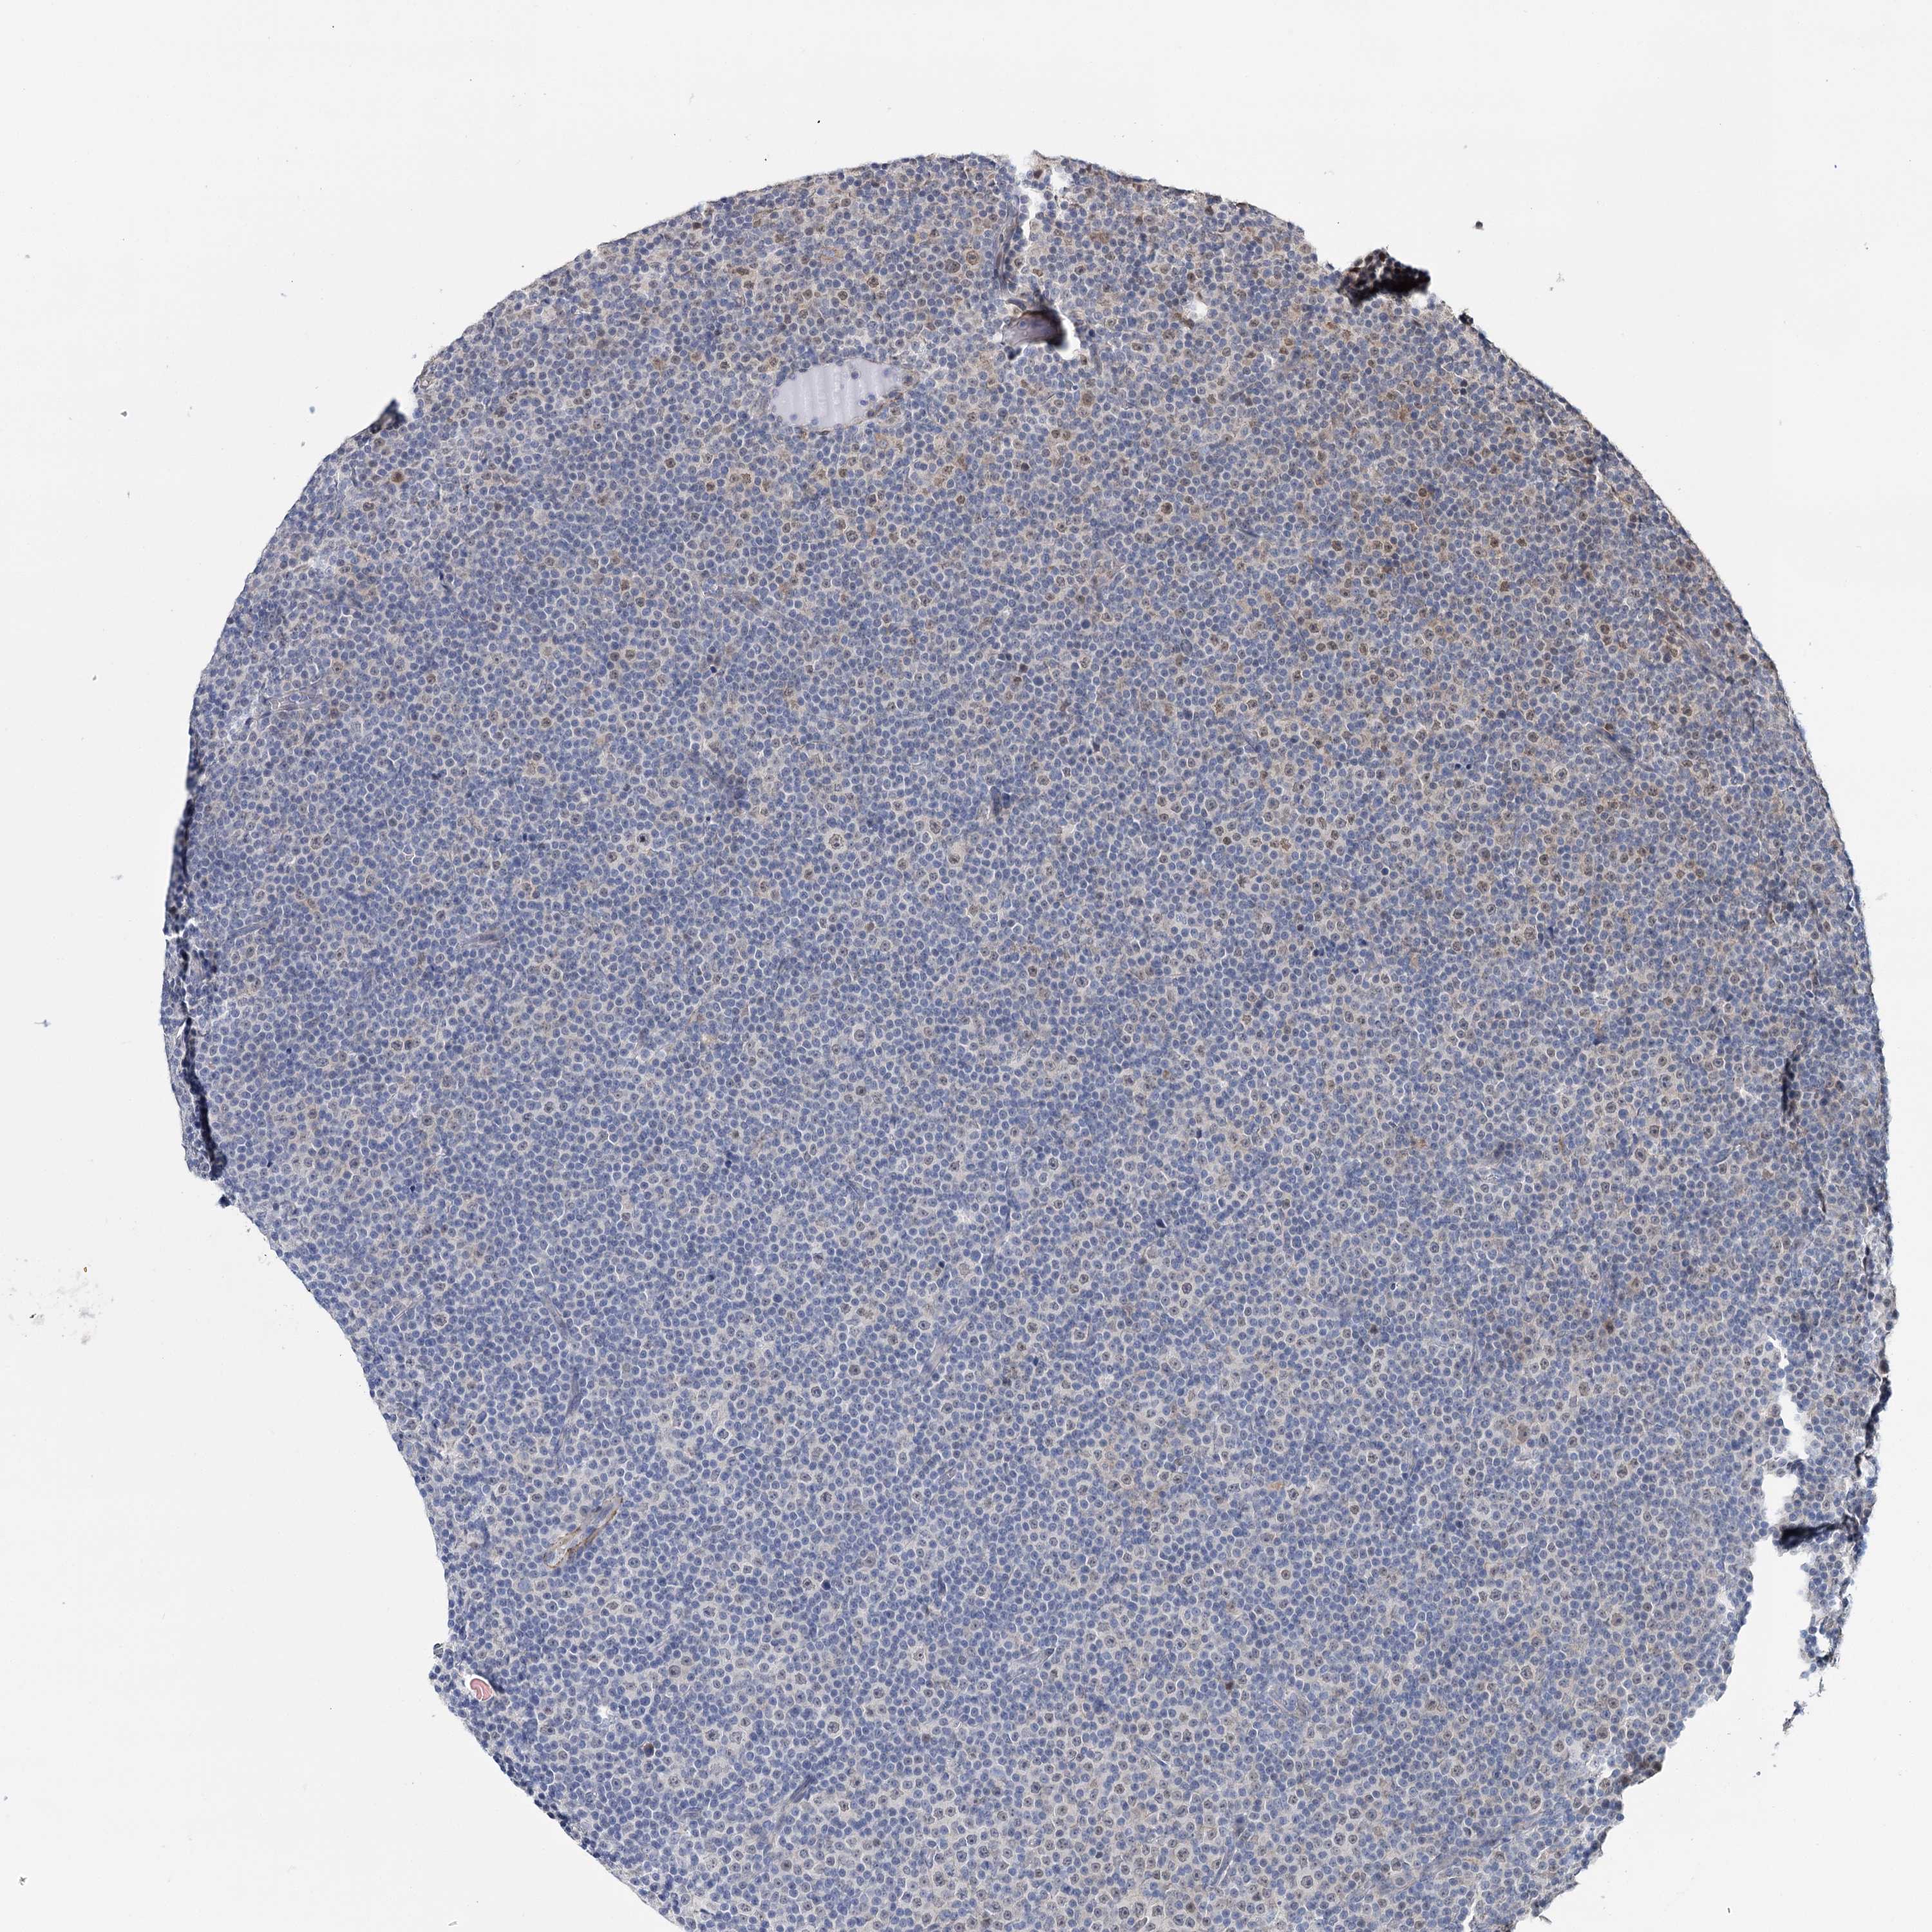

CANCER LYMPHOMA Show tissue menu

LYMPHOMA - Protein expressioni

A mouse-over function shows sample information and annotation data. Click on an image to view it in a full screen mode. Samples can be filtered based on level of antibody staining by selecting one or several of the following categories: high, medium, low and not detected. The assay and annotation is described here.

Each image is clickable and will lead to virtual microscopy that enables deeper exploration of all samples and also displays staining intensity scores, fraction scores and subcellular localization as well as patient and tissue information for each sample.

Antibody HPA037786

Hodgkin's disease, NOS

Malignant lymphoma, non-Hodgkin's type, High grade

Malignant lymphoma, non-Hodgkin's type, Low grade